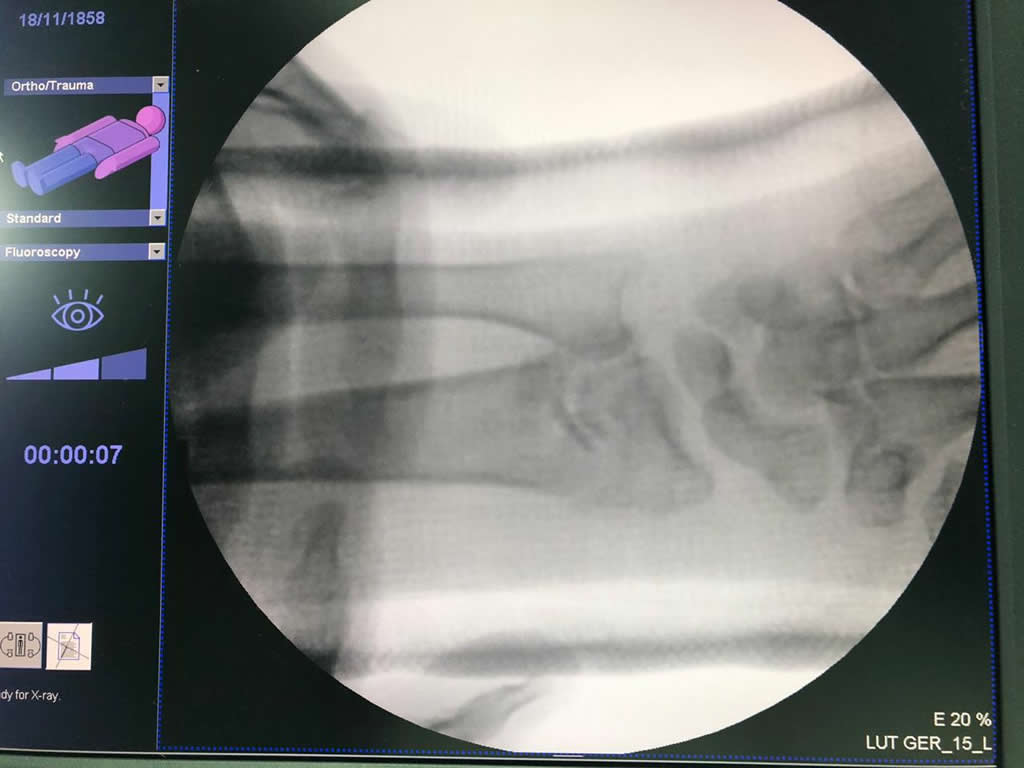

Cirugía de Fémur - Cirugías de Muñecas y Manos

Los procedimientos más comunes en cirugía de la mano son aquellos destinados a reparar traumatismos, incluyendo lesiones de tendones, nervios, vasos sanguíneos, y articulaciones; huesos fracturados; y quemaduras, cortes, y otros daños de la piel.